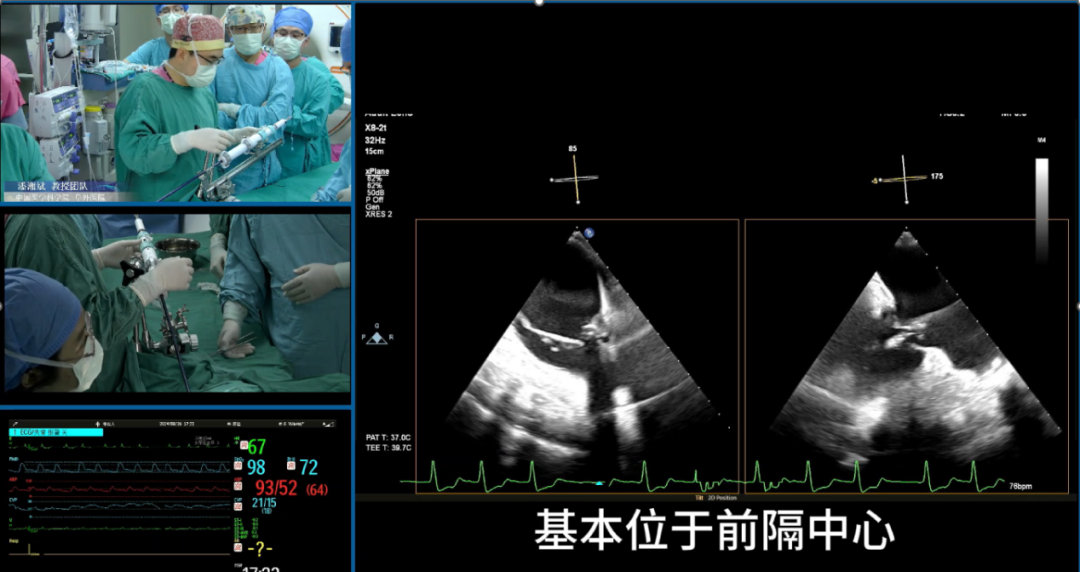

施浩教授介绍了一例成功进行单纯超声引导下经导管三尖瓣置换术的病例,从术前CT评估,术前3D打印体外模拟多方面详细介绍了术前评估流程,并且展示了术中超声过程。

赵广智教授以两例成功进行全超声引导下三尖瓣TEER的病例为例,详细介绍了该技术的术中操作步骤,提供了超声引导三尖瓣TEER的技巧和建议,包括探头操作和多级成像。